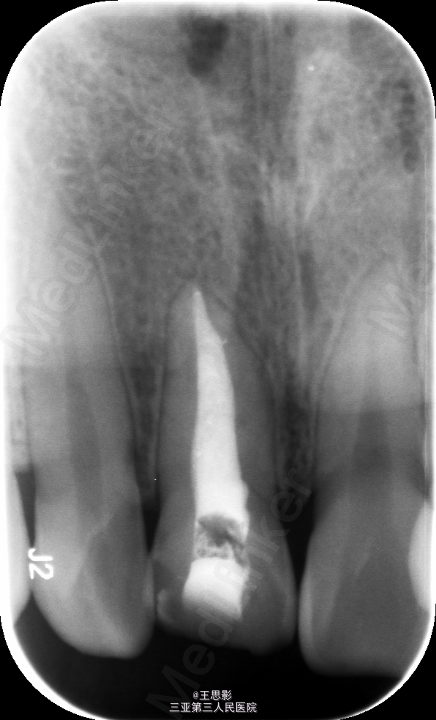

11牙体缺损,根充不良,处理,去除原充填物,再治疗锉去除牙胶,预备后,试尖,欠长1mm,重新H锉疏通,到达长度后,以大锥度牙胶完成热压充填